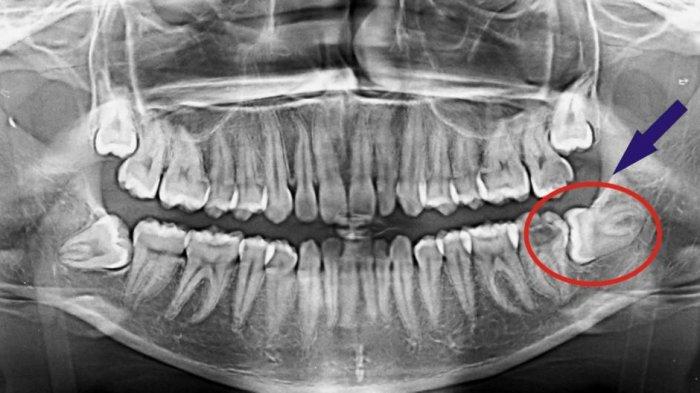

Impaksi gigi adalah kondisi di mana gigi terjebak di dalam gusi sehingga pertumbuhannya tidak sempurna.

Kondisi ini biasanya terjadi pada gigi bungsu orang dewasa.

- Gigi menjadi bengkok atau miring ketika berusaha tumbuh

- Rahang terlalu kecil sehingga tak cukup ruang untuk pertumbuhan gigi

- Gigi lain sudah tumbuh dalam posisi yang tidak beraturan sehingga menghalangi gigi bungsu

Impaksi gigi tidak hanya terjadi pada gigi bungsu

Menurut Dr. drg. Munawir H. Usman, SKG., MAP impaksi seringkali terjadi pada gigi bungsu meskipun bisa terjadi pada gigi-gigi lainnya.